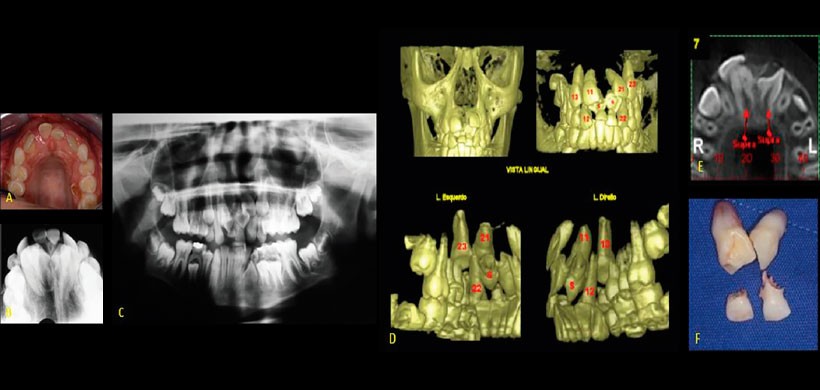

Fig 1. Fotografía clínica, radiografía oclusal y radiografía panorámica que evidencian la presencia de un diente supernumerario en la zona anterosuperior provocando el retraso de la erupción de los dientes permanentes.

Fig 2. Renderizado 3 D, se muestra la presencia de un diente supernumerario localizada en el raffe medio a un nivel bien posterior. Nótese que pasa desapercibido en la radiografía panorámica